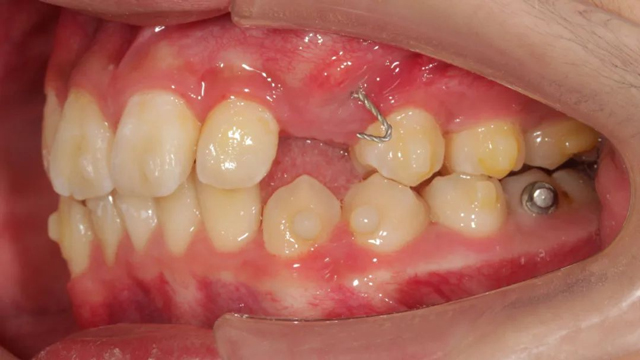

談到具體的治療方案,王亞楠醫生表示,整體的治療步驟是先拔除多生牙,一周后拆線,拆線當天拔除滯留乳牙,并對埋伏阻生尖牙行開窗術,通過粘貼牽引扣進行牽引,一周后開始佩戴隱形牙套。

據介紹,這個病例最復雜之處就是阻生牙的牽引。從矯正開始,醫生以目標為向導制定矯正步驟,利用隱形牙套的優勢,以及牙根可視化引導牙齒走向目標位,過程中密切關注阻生尖牙的方向及萌出情況,治療過程中不斷根據具體情況進行調整牽引方向和力的大小,牽引治療幾乎貫穿了矯正的全過程。

“由于這是一顆尖牙,外形比較圓潤,并且是口內牙根最長的牙齒,矯治器力不太容易表達,所以移動時會更難一些,從牙齒出齦到建頜,每一步都離不開我們精心的設計。”